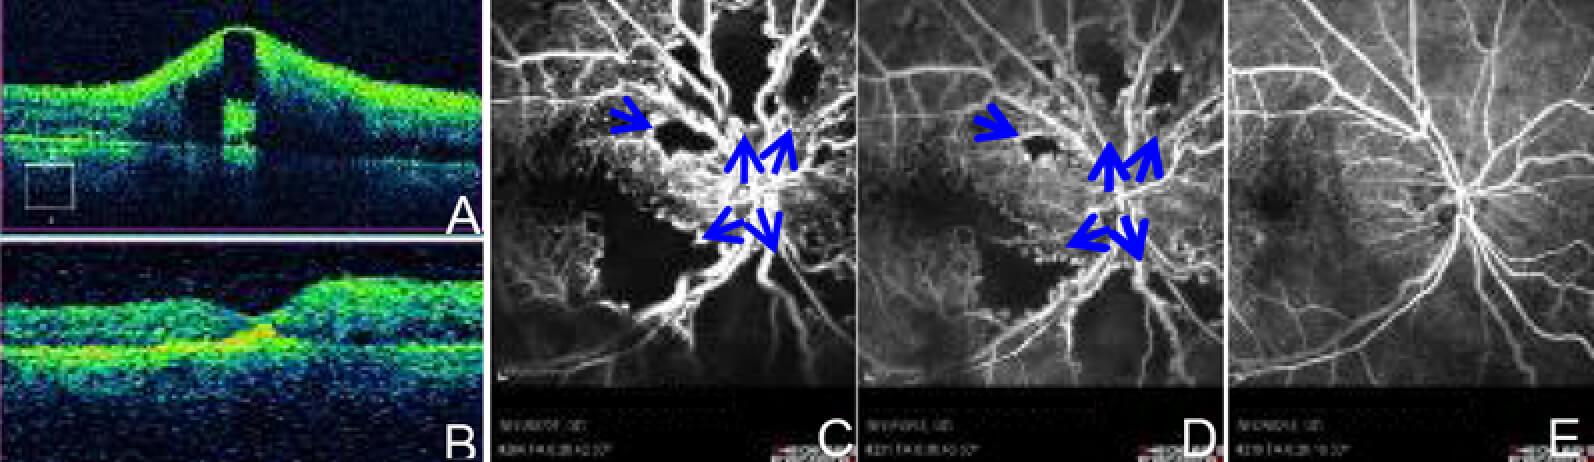

我々は活性型プロテインC(APC: Activated Protein C)の虚血網膜に対する効果を検討した結果、網膜細胞保護効果を見出しました(Invest Ophthalmol Vis Sci. 52:987, 2011)。そして、高度虚血型網膜中心静脈閉塞症を対象としたAPC眼内投与の医師主導型臨床試験の結果、広範囲の無灌流領域が再灌流する現象が、約6割の症例で見られました(図1、2)。広範囲の網膜血行再建に成功した世界初の報告となりました(JAMA Ophthalmol.132:361, 2014)が、再灌流の詳細なメカニズムは不明です。

投与前(A)、および投与後1ヶ月(B)の網膜断層撮影。APC投与により網膜浮腫が完全に吸収されています。蛍光眼底造影(C-E)では、投与前(C)に見られた無灌流領域(矢印)が投与後3ヶ月(D)では面積比で58%減少し、投与後10か月(E)では完全に再灌流していました。